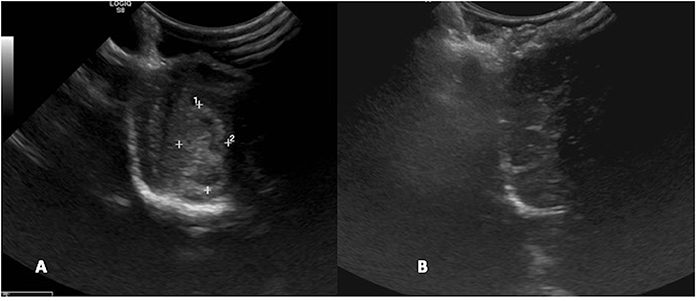

FIGURE 2

Figure 2. Case 24. There is an ovoid, well-circumscribed, 1.65 cm by 1.80 cm (MRI)/1.83 × 1.75 cm (US), heterogeneous, centrally hyperechoic and rim hypoechoic mass present in the right cerebrum, which results in medial displacement of the ultrasonographically normal brain parenchyma. There are a few pockets of anechoic fluid present medial and caudal this mass. This mass was a high-grade oligodendroglioma.

Figure 5. Case 1. Left, a transverse T1 + Contrast image of a meningioma. Right, a sagittal intraoperative ultrasound showing the mass () and adjacent lateral ventricle ().